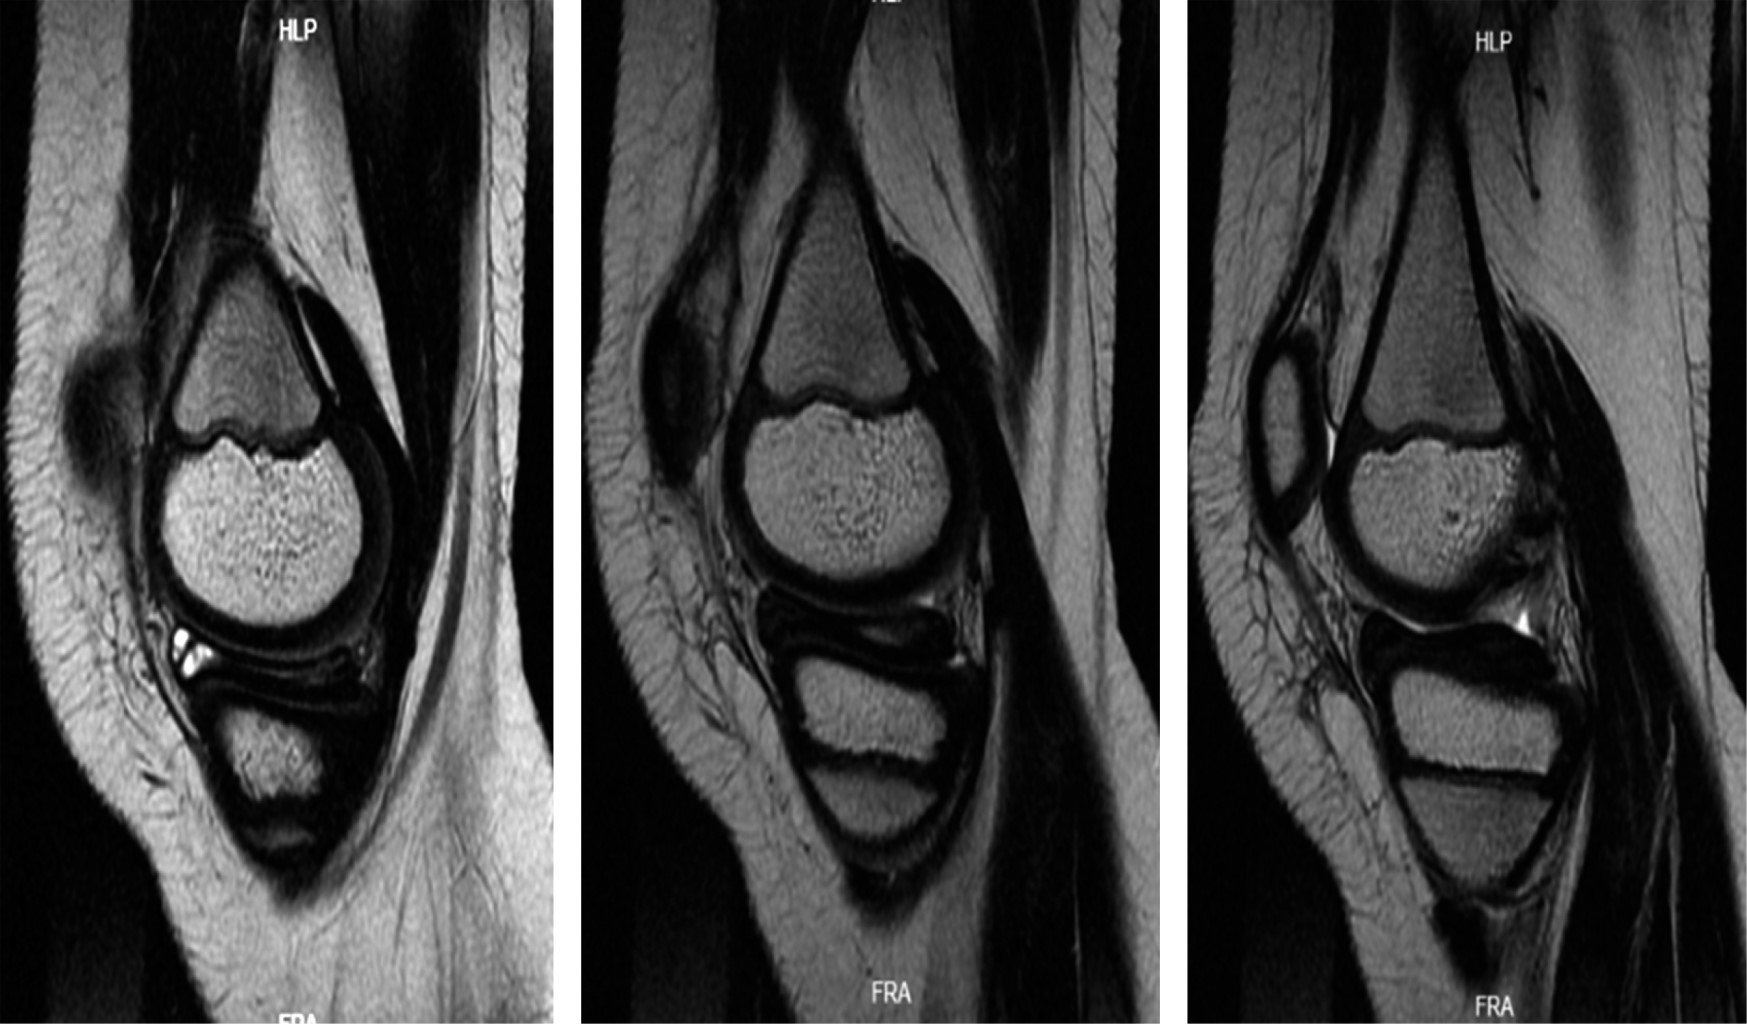

Se solicitó una resonancia magnética simple de la rodilla, que reveló una lesión de grado 3 en el menisco medial, bursitis suprarrotuliana y edema en los tejidos blandos de la parte anteromedial de la rodilla. Además, se identificó una lesión en el menisco medial con una morfología aparentemente discoidal, indicada por la presencia del "signo del corbatín" (Figuras 1 y 2).

Figura 1

Figura 2